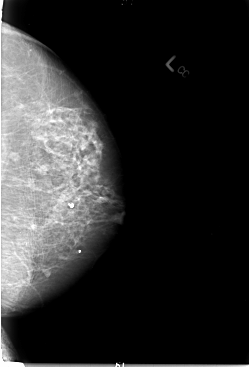

B_3025_1.LEFT_CC

LEFT_CC LINES 5864 PIXELS_PER_LINE 3984 BITS_PER_PIXEL 12 RESOLUTION 50 NON_OVERLAY